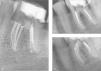

Primer molar inferior con cinco conductos, tres mesiales y dos distales. (a) Radiografía postoperatoria (ortoangulada). (b) Radiografía postoperatoria (mesioangulada). (c) Radiografía de seguimiento 2 años después del tratamiento. Se observa que se ha colocado un poste en uno de los conductos radiculares mesiales.

Secuencia in vitro de la modificación de la apertura de acceso para la localización de los conductos distocentral y mesiocentral. (a) La cámara pulpar después de la localización y preaplanado de los cuatro conductos principales. (b) Se emplea una pequeña punta ultrasónica para eliminar las paredes laterales de dentina entre los dos conductos principales de la raíz mesial. (c) Observación del istmo normalmente presente entre los dos conductos. (d) Después de los procedimientos anteriores, se intenta permeabilizar a través del acceso mesiocentral con limas pequeñas, que pueden centrarse o acercarse a uno de los conductos principales. (e) Cuando la raíz distal presenta dos conductos principales, se realiza el mismo procedimiento descrito para la raíz mesial. (f) Se han encontrado tres conductos en la raíz distal. Los dos más grandes ya se han preparado completamente; la raíz distocentral se ha instrumentado con una lima del número de 10.

Todas las raíces mesiales presentan una concavidad istal y son más estrechas mesiodistalmente. El conducto mesiovestibular es el más cercano a la superficie externa de la raíz y presenta además curvaturas más pronunciadas que el conducto mesiolingual47,48. Por ello, en los casos de confluencia y salida común es mucho más seguro y fácil clínicamente instrumentar el conducto mesiolingual hasta la longitud de trabajo y el conducto mesiovestibular hasta el nivel de la confluencia. Identificar y comprender la configuración interna de los conductos mesiales guarda relación también con la preparación apical. Marroquin et al.49 reseñaron que cuando el foramen apical es común, el tamaño medio del diámetro máximo es 0,31mm. Por el contrario, cuando encontramos dos foraminas separadas, el diámetro máximo medio no excede los 0,25mm. Estos datos sugieren que con una configuración tipo II, el operador debe escoger una lima maestra apical mayor que cuando trata una configuración tipo IV, que permite una preparación más conservadora. De cualquier forma, la preparación de los conductos debe correlacionar siempre con la anatomía y el estado microbiológico del conducto. Así mientras que los casos vitales deben tratarse de forma más conservadora, los casos que presentan infección pueden requerir preparaciones apicales más grandes para permitir una irrigación y desinfección eficientes50. Desde que se describió por primera vez la presencia de tres conductos en la raíz mesial son varias las publicaciones que han tratado sobre ello51,52. Nuestra revisión sistemática de la literatura incluyó 4.535 raíces mesiales y reseñó una incidencia del 2,6% (figs. 7 y 8) del tercer conducto25. Para poder localizarlo es necesario realizar modificaciones en el acceso. La figura 9 ilustra el procedimiento requerido para encontrar un tercer conducto tanto en la raíz mesial como en la distal (fig. 9). De forma breve; una vez localizados los conductos principales e instrumentados sus accesos, se emplean fresas pequeñas o puntas ultrasónicas para eliminar el puente dentinario que comunica ambas entradas. Este paso tan simple permite obtener una visión directa del ángulo formado por la pared mesial y el suelo de la cámara pulpar y exponer el surco del desarrollo que se encuentra entre los dos conductos principales (fig. 10). Se emplea a continuación un explorador de endodoncia intentando luego permeabilizar el posible tercer conducto con limas pequeñas. El empleo de microscopios clínicos mejora la posibilidad de hallar y tratar estos conductos accesorios53. Teniendo en cuenta la concavidad distal de la raíz mesial, la instrumentación del tercer conducto medial debe realizarse cuidadosamente con instrumentos pequeños para evitar perforaciones por desgaste38(stripping). La morfología interna de este tipo de raíz mesial es muy variable, y nunca se debe descartar la posibilidad de que exista un conducto totalmente independiente en hasta un 25% de los casos25.